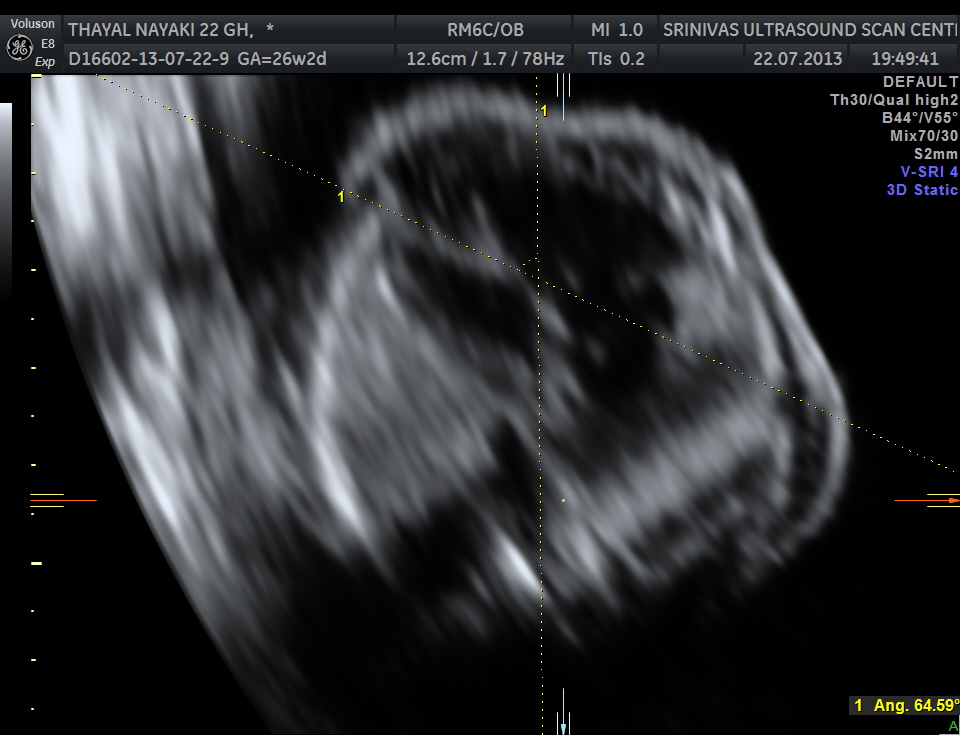

The cardiac axis appeared to be abnormal .

4 chamber view is given below .

3 vessel view shows a prominent single vessel , which is very suggestive of outflow tract anomalies like transposition of great arteries, double outlet right ventricle , truncus arteriosus and corrected transposition of great arteries.

another view of the above two